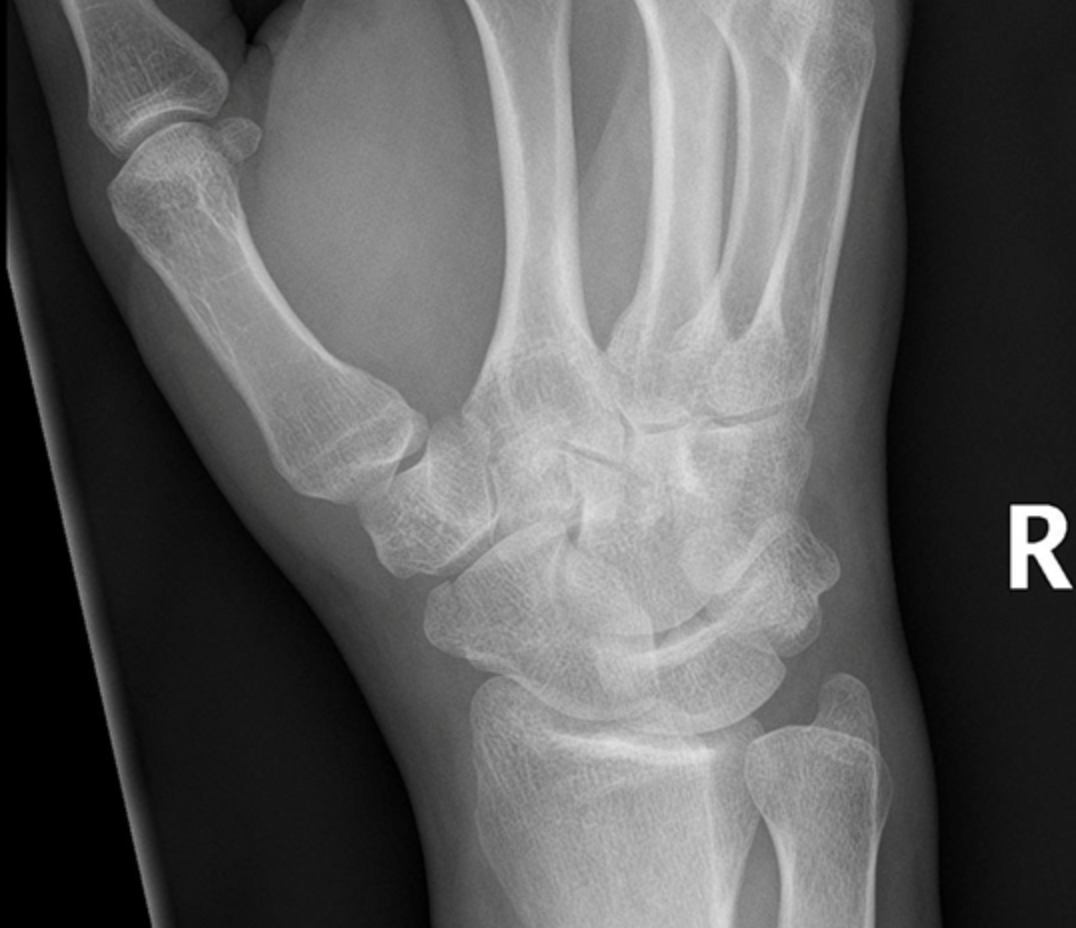

Describe the pathology here…

Right distal undisplaced Scaphoid Fracture

How to you manage a scaphoid fracture initially?

Immobilisation in a thumb spica cast

(or Immobilisation of the fracture in a below elbow / short arm / scaphoid cast)